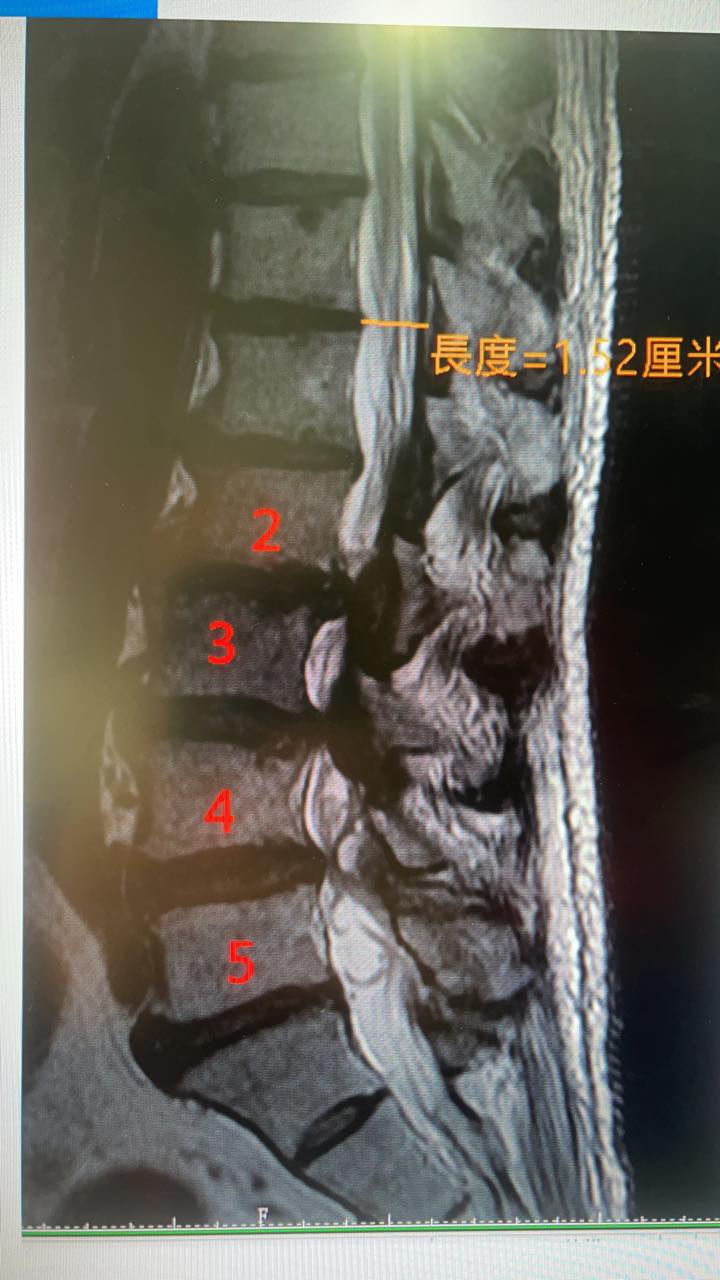

PS.原本腰痛到差點輕生的患者,很難想像腰椎嚴重狹窄會把人折磨到不成人形,體重暴瘦七公斤 !